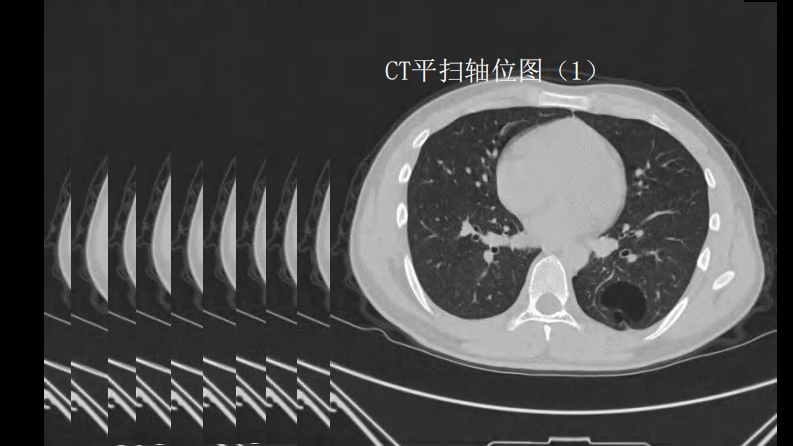

这样的肺隔离症:影像共享.pdf